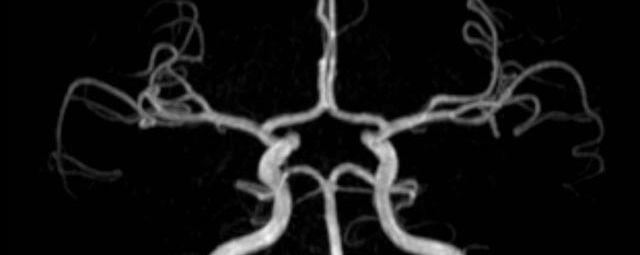

- MR-Angiografie ohne Kontrastmittel

- Time of Flight (TOF)-Angiographie

- Phasenkontrastangiographie (PCA). Geeignet zur Quantifizierung Stenose-/Insuffizienzgrad z.B. bei Herzklappen, falls echokardiographisch die Untersuchungsbedingungen eingeschränkt sind.

Je nach Fragestellung und Körperregion Gefäßdarstellung ohne Kontrastmittel bei Kontrastmittelunverträglichkeit oder terminaler Niereninsuffizienz möglich.